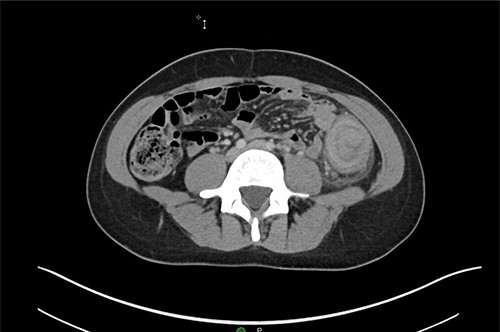

A 31-year-old woman initially presented to the ED with 2 days of left flank pain and a 1-year history of abdominal pain and bloating. The patient reported having had a fever (100.5 Tmax) and recurrent non-bloody loose stools. Vitals upon presentation to the ED were reassuring and the patient was afebrile. Initial physical exam was normal with the exception of costovertebral angle tenderness. Labs were significant for elevated c-reactive protein and leukocytosis. CT abdomen revealed segmental wall thickening of the descending colon with adjacent inflammation and associated with diverticular disease favoring acute diverticulitis (Figs 1 and 2). There was no evidence of nephrolithiasis. The patient was discharged on a 7-day course of Augmentin and was scheduled for colonoscopy.

Axial CT demonstrating segmental wall thickening of the descending colon with adjacent inflammation favoring acute diverticulitis or segmental colitis.